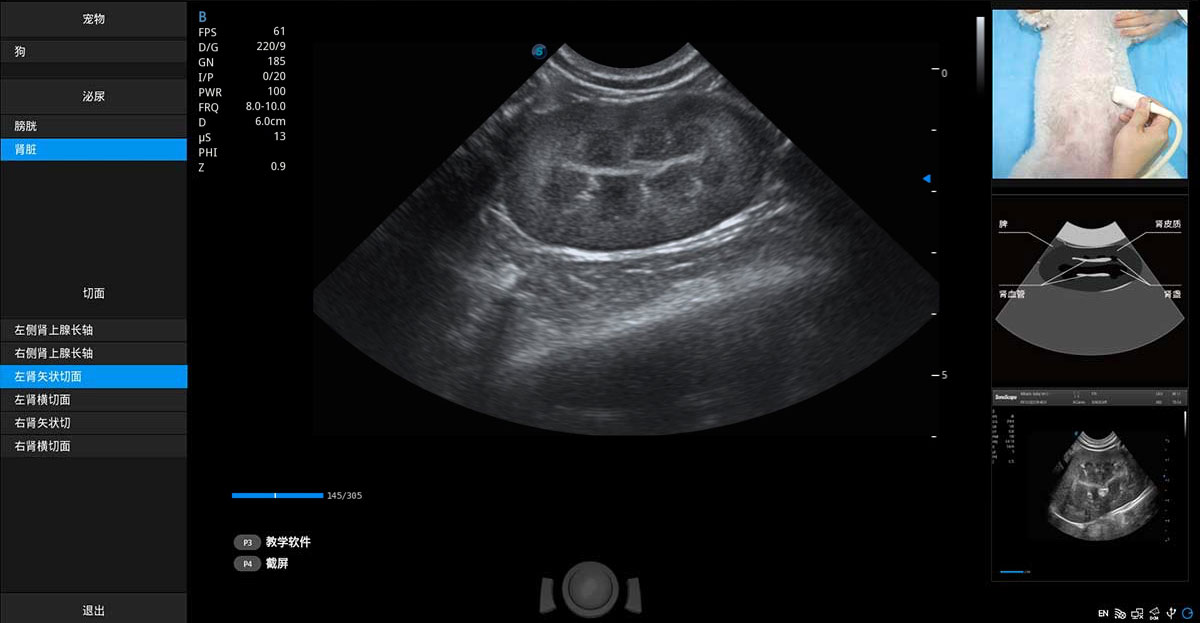

提供解剖示意图、标准超声图像、扫查手法图和操作者实时检查图像,指导操作者进行标准切面的正确扫查。